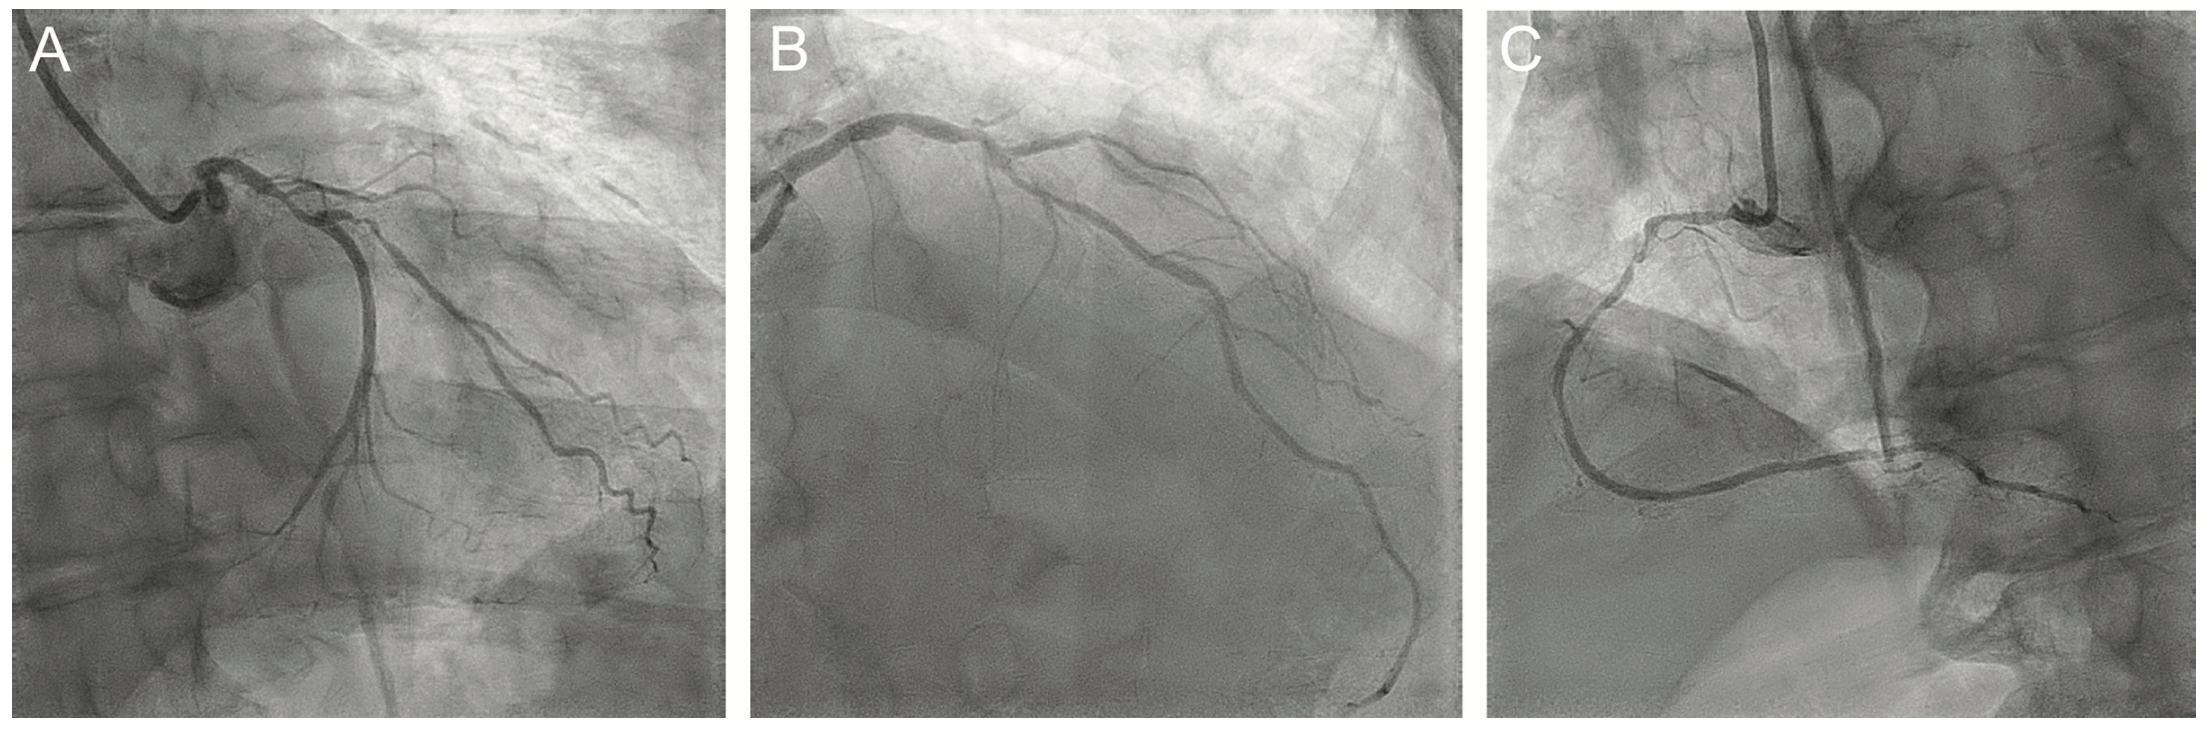

A 77-year-old man with hypertension, hyperlipidemia, diabetes mellitus, and chronic kidney disease stage 3 presented to our hospital with progressive angina. He underwent stress testing that showed an area of inferior ischemia as well as transient ischemic dilatation concerning for multivessel coronary artery disease. Diagnostic coronary angiography showed severe calcific disease of the left anterior descending artery (LAD), a diffusely diseased left circumflex (LCx), and a critical ostial stenosis of the right coronary artery (RCA) (Figure 1A-C). The patient was evaluated for coronary artery bypass graft surgery but determined to be at prohibitive risk for open heart surgery. We proceeded with planned multivessel percutaneous coronary intervention in staged sessions due to the patient’s underlying kidney disease.

We proceeded with intervention to the RCA via right radial access using a 6 French (Fr) Terumo Glidesheath. Due to the critical ostial stenosis, a Terumo Runthrough wire was loaded in a 6 Fr Judkins right (JR)4 guide. There was severe pressure dampening on guide engagement and the wire was quickly advanced into the distal RCA. We attempted to deliver 2.5 and 2.0 mm Takeru semi-compliant balloons, but the balloons would not cross the proximal RCA stenoses. We then used a 1.5 mm Takeru semi-compliant balloon and dilated the ostial and proximal RCA, followed by 2.0 and 2.5 mm noncompliant balloons at 14 atmospheres (atm) (Figure 2). The ostial lesion was further dilated with a 2.5 x 10 mm Wolverine cutting balloon (Boston Scientific) at 8 atm. Intravascular ultrasound (IVUS) was performed with a Refinity catheter (Philips) (Figure 3A), and using a 6 Fr Guideliner (Teleflex), 2.5 mm x 38 mm and 2.5 mm x 22 mm Onyx Frontier drug-eluting stents (Medtronic) were deployed from the ostium to the mid RCA at 12 atm. The stents were post dilated with 3.0 and 3.5 mm Takeru noncompliant balloons at 18 atm. There was an excellent angiographic result with no residual stenosis (Figure 4A). IVUS showed well-expanded and well-apposed stents without evidence of dissection (Figure 3B), and the ostial RCA minimal stent area was 10mm2. The entire intervention was performed with only 65 mL of contrast dye. The patient was maintained on dual antiplatelet therapy with aspirin 81 mg and clopidogrel 75 mg daily. The patient returned for staged intervention to the LAD with rotational atherectomy and intravascular lithotripsy (Shockwave Medical) (Figure 4B).